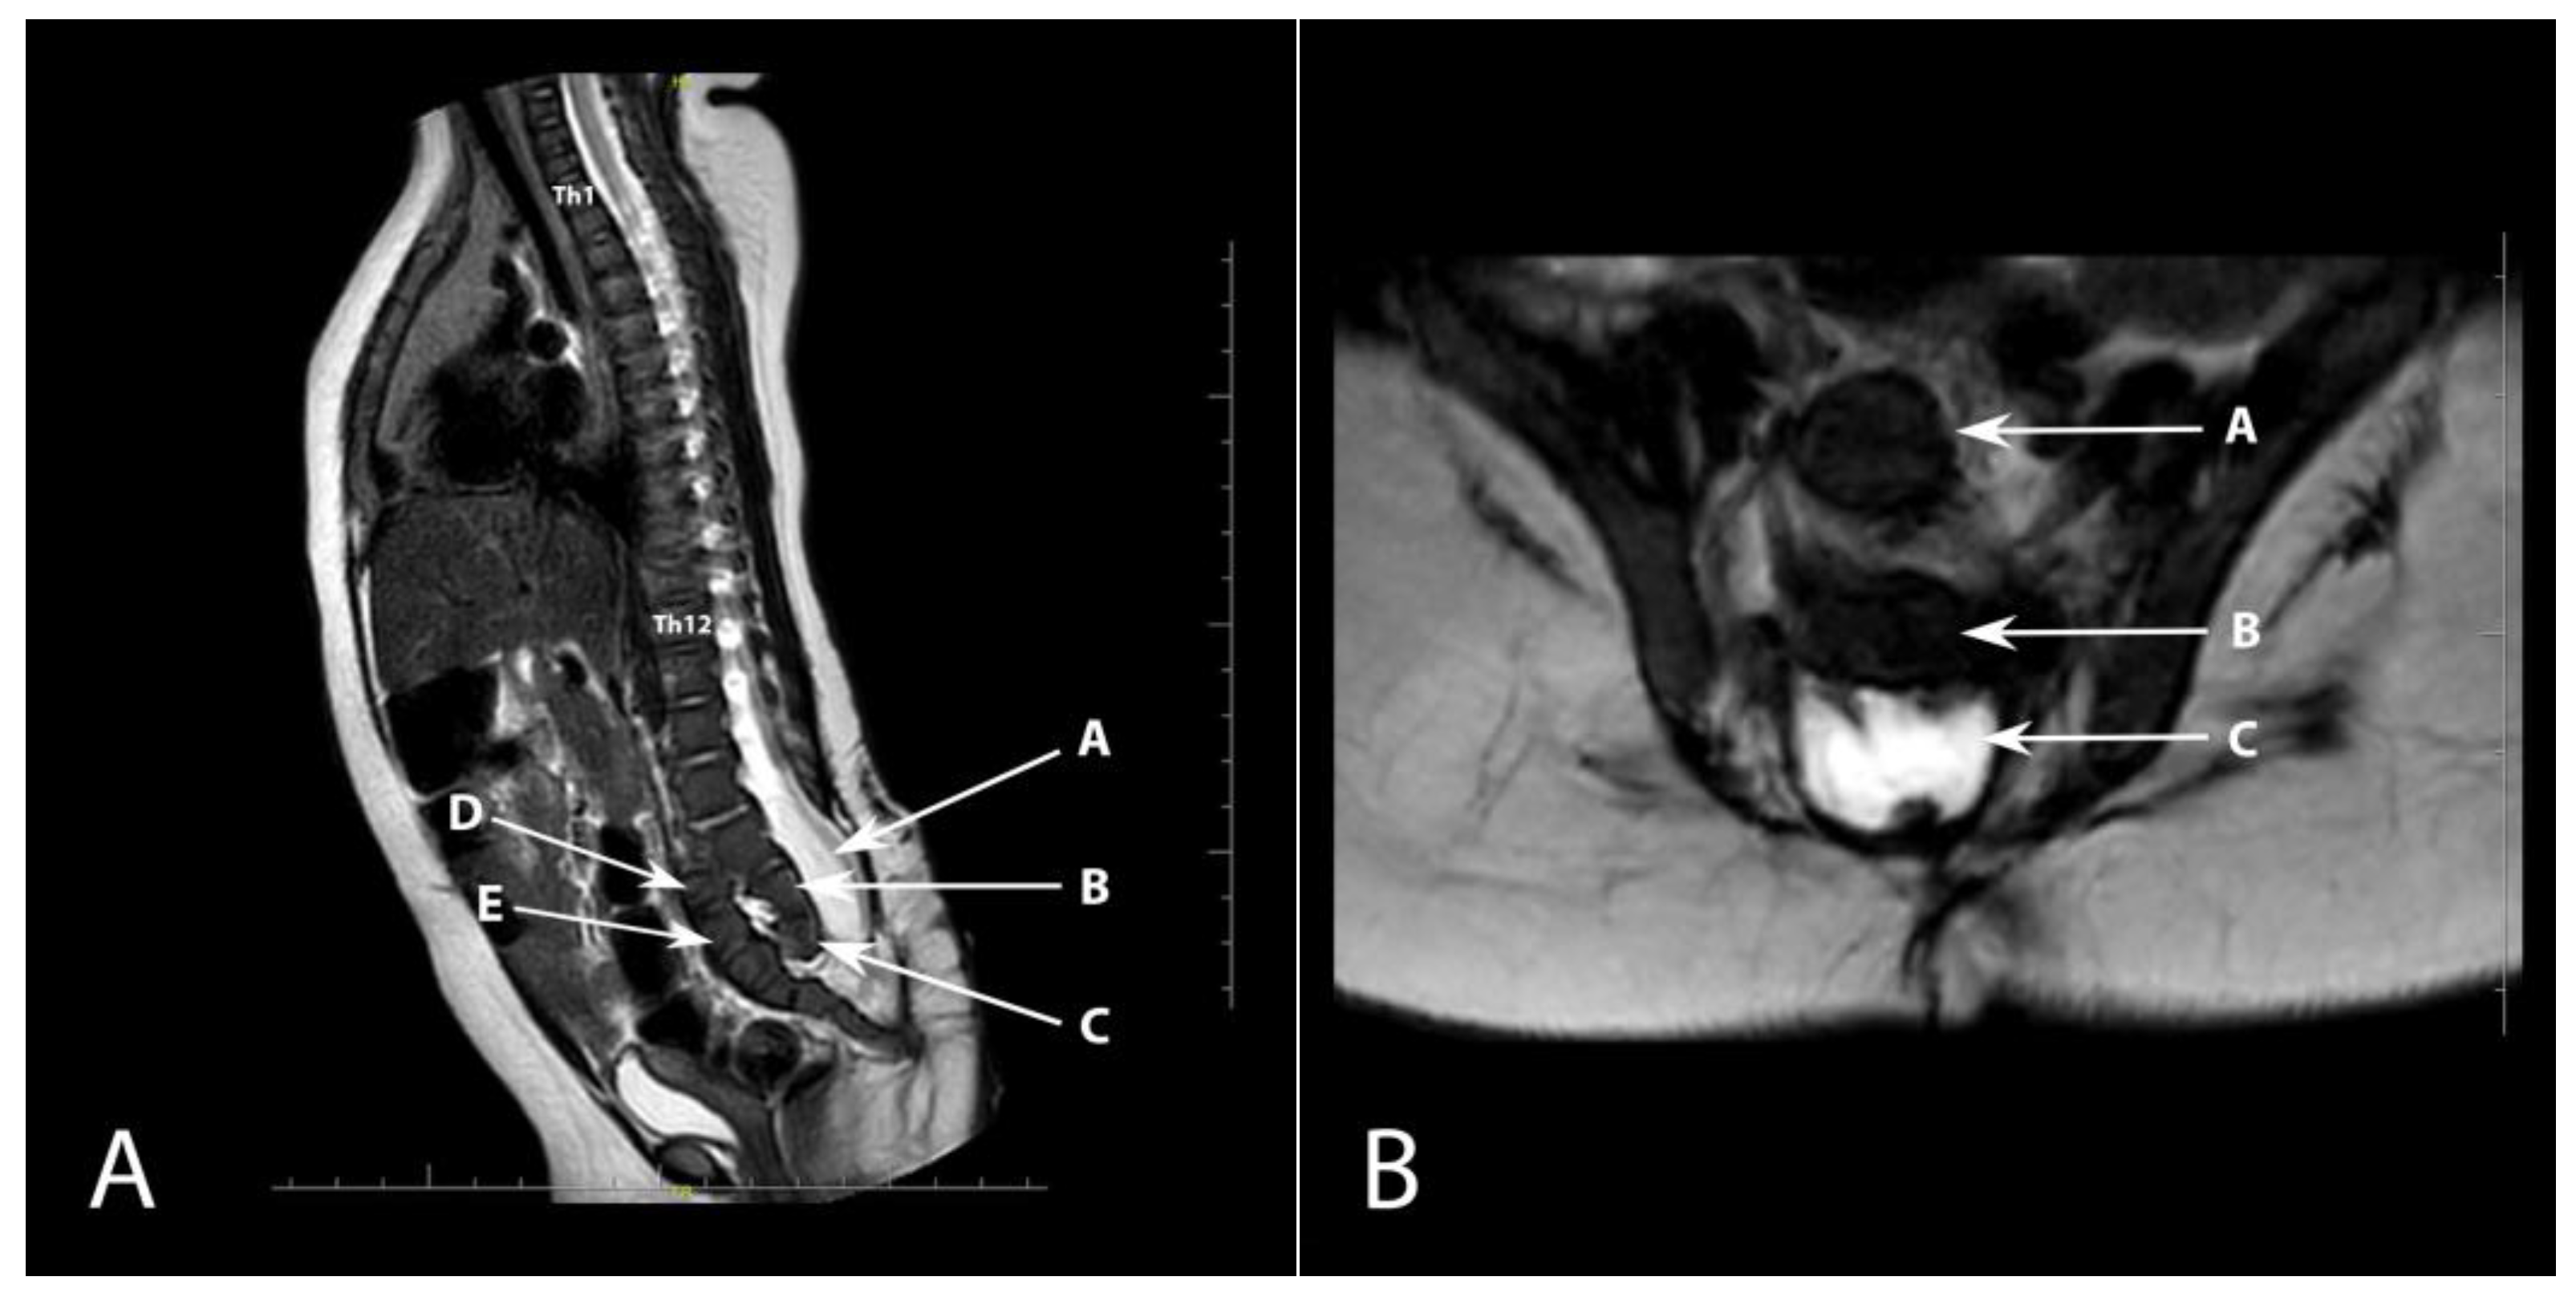

The child was qualified for a hernia repair surgery. A medical rehabilitation specialist diagnosed the lower limbs positioned in flexion and adduction at the hip joints (trace movement), extended in the knee joints (trace flexion—more frequently in hyperextension), and feet in a stable equinovarus position. The patient’s CT scan confirmed ventriculomegaly without evident signs of active hydrocephalus. Ultrasound examination did not reveal any residual urine in the bladder after voiding. In the follow-up physical examination, there was a depression of the skin on the right side of the surgical scar after closing the open myelomeningocele. An MRI examination was performed to exclude the presence of a dermal sinus, which revealed a developmental defect of the sacrococcygeal bone (Figure 2). Despite recommendations for further diagnostics, the patient did not attend the required follow-up examinations.

Figure 2.

(A). Sagittal plane MRI T2-weighted sequence showing anterior dislocation of the sacrococcygeal bone (arrow). Th1 and Th12 vertebrae are also marked. A—open spinal canal, B—L5 vertebra, C—hypoplastic S1 vertebra, D—hypoplastic S2 vertebra, E—S3 vertebra; (B). Axial plane T2-weighted MRI sequence. A—S3 vertebra, B—L5 vertebra, C—open spinal canal.